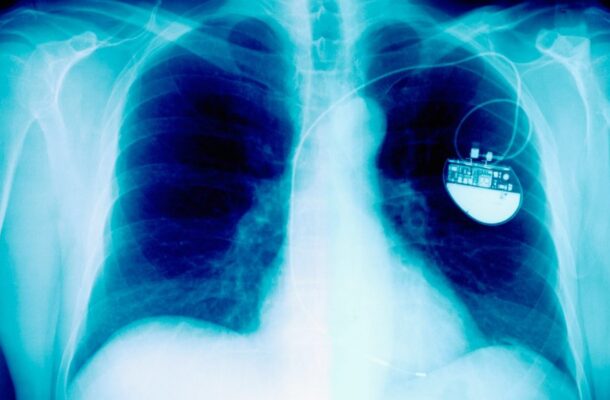

A new pacemaker has shown the potential to fundamentally alter how a failing heart works, offering renewed hope to millions living with heart failure. In a study described by researchers as both unexpected and promising, scientists have found that the device does more than correct irregular heartbeats. Instead, it appears to reprogramme the heart’s energy system, helping it recover strength and function by changing how it fuels itself.

The study focused on a specialised device known as cardiac resynchronisation therapy, or CRT, a type of pacemaker already used in some heart failure patients. What surprised researchers was how rapidly the device influenced the heart’s metabolism.

Fourteen patients with heart failure took part in the trial, all of whom were fitted with the CRT pacemaker. Over the following six months, researchers closely monitored changes in heart structure, performance, and patient wellbeing.